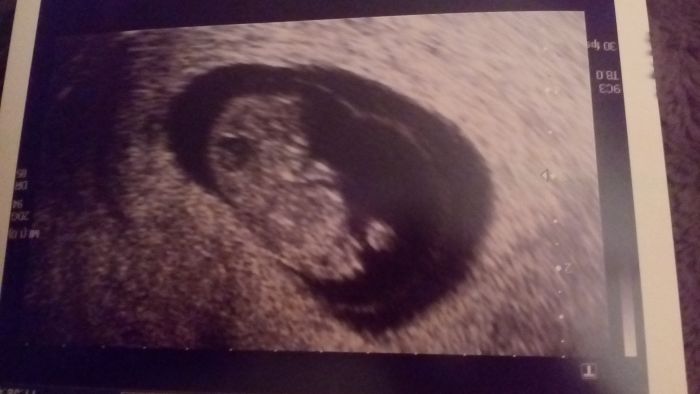

ahoj ženy...tak jak jsem slíbila,před chvíli jsme se vrátila z Veveří ze sreeningu..miminko vypadá ok,ale k našemu překvapení je to chlapeček.

Cekali jsem podle Mudr.holčičku

,odpoledne budou volat ještě krev.Vyšetřovala Mudr.Pavková a byla velice příjemná.Takže tak